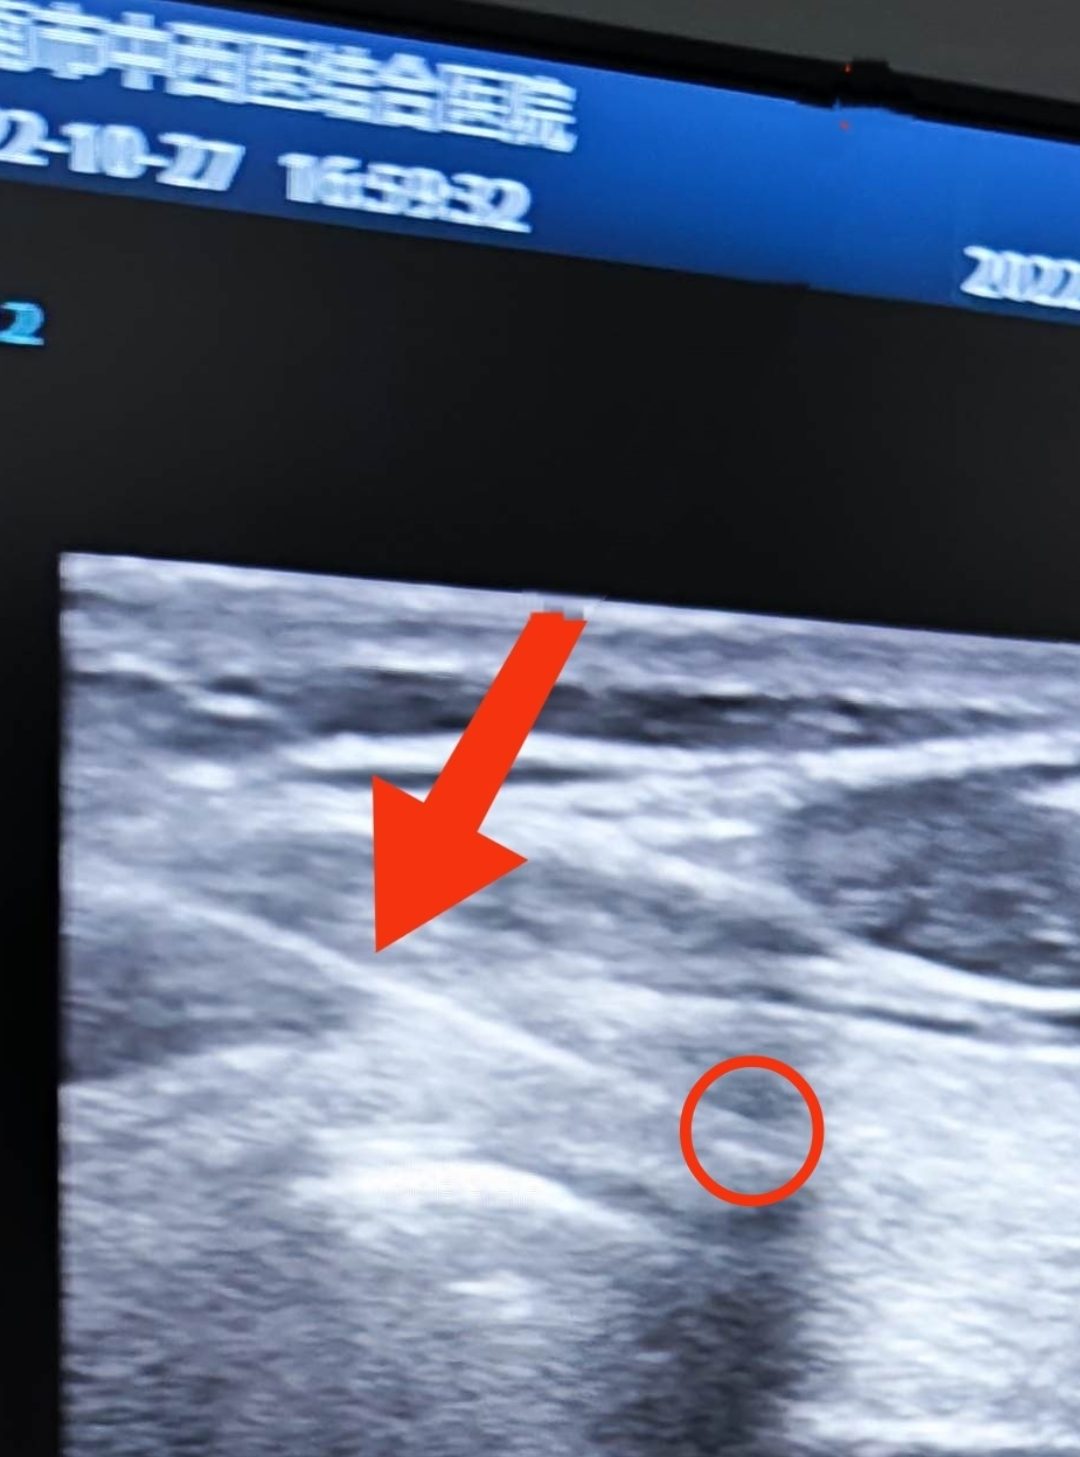

上(shàng)周五,門診一(yī)名女(nǚ)性患者來(lái)診,查體(tǐ)彩超發現(xiàn)甲狀腺結節

如(rú)下(xià)圖

放(fàng)大圖像